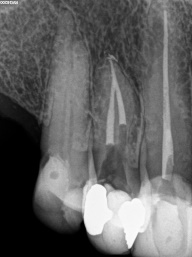

Em dentes de pessoas jovens, o canal é largo (amplo), com o decorrer do tempo e o envelhecimento natural, os canais vão diminuindo a sua luz ( o espaço interno ), tanto pela deposição continua de dentina, quanto por influências do meio externo, como trauma oclusal, caries, restaurações, e outros, com tudo isso, pode ocorrer desse espaço interno do dente ficar muito estreito (atresiado) ou até sumir por completo, ou seja completamente calcificado, quando chega nessa situação, é necessário o trabalho do endodontista para a localização dos canais calcificados e ou atresiados, limpeza e obturação com material indicado em cada caso.

Nos dias de hoje, existem técnicas e equipamentos que ajudam o profissional a conseguir o melhor resultados nessas situações, e uma delas é o uso do microscópio, que ajuda na localização das entradas dos canais atresiados e calcificados com maior precisão e segurança para o paciente.